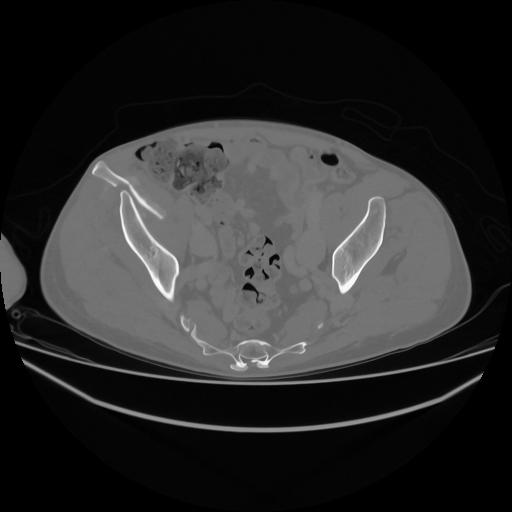

5 CUERPO,CE,Vol,1.0,CUERPO,,